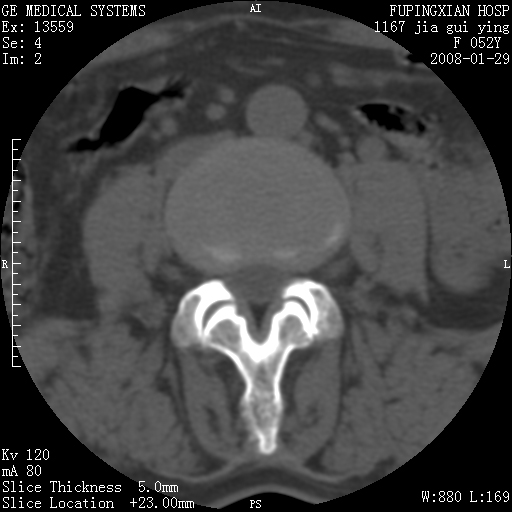

以下是引用dyqct在2008-1-29 21:49:00的发言:[br]考虑:1、腰4-5椎间盘突出(左椎间孔外侧型)。[br] 2、硬膜囊内钙化,多考虑蛛网膜炎所致粘连钙化,请询问病史病人以往做过碘油造影吗?

以下是引用liuyue在2008-1-30 4:32:00的发言:[br]1. 腰4-5椎间盘突出。[br]2. 硬膜囊内钙化,考虑a.蛛网膜炎所致粘连钙化;[br] b.硬膜囊内血管畸形.[br] c脊髓纵裂畸形.[br] 另:询问病史病人以往做过碘油造影吗?